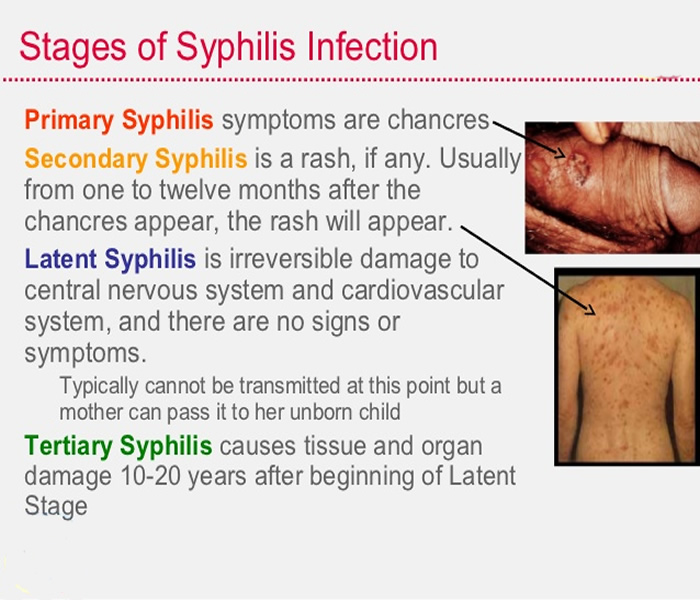

Stages of Syphilis: Symptoms, Causes, Prevention, and Treatment

Syphilis

Syphilis on emaze

Signs and Symptoms – syphilis-the great imitator

Syphilis